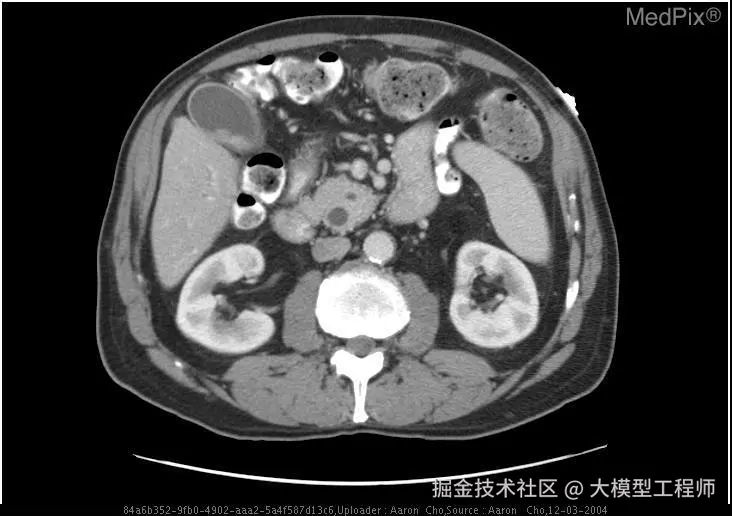

🔍 效果展示

🚀 input:下面是 CT 医疗问诊的问题以及 CT 图像初步诊断。问题:does the gallbladder appear distended?;图像初步诊断:yes;

🧰 output:

可以看到小助手召回了相关片段并给出了回答!

通过微调 + RAG,LLM 不再「闭门造车」,而是真正拥有了「读万卷书 + 亲临临床」的实力,成为你身边靠谱的「AI 医学助理」!